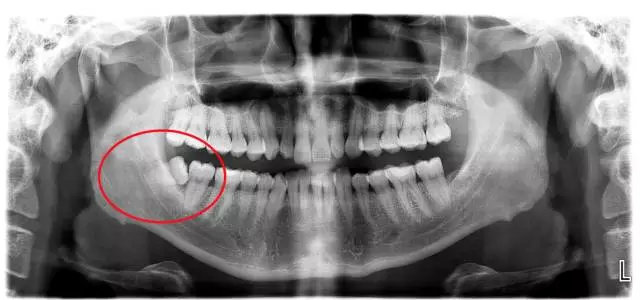

这种情况你只有通过拍摄口腔全景片才能看清:

你是不是也很好奇自己的智齿长什么样,拔除要多少钱?赶紧给口腔做一个全面检查,拍一个口腔全景片吧,不仅可以了解你的全面口腔健康情况,还能知道,你的智齿生到底长啥样。